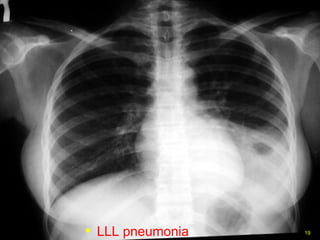

LLL pneumonia